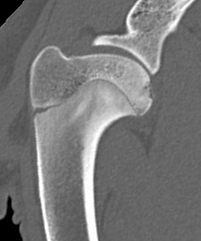

CT scan of a dog shoulder showing an OCD lesion (star).

OCD lesions are usually visible on good-quality radiographs (X-rays), especially in typical joint locations. CT scans may be used to better define the size, shape, and exact location of the defect — helpful for surgical planning. Arthroscopy allows direct visualization of the lesion and confirmation of cartilage flap formation.